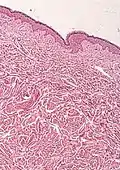

Microscope with stained slide (histological specimen)

Histopathology of BOS.[12]

• Histological test